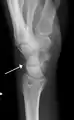

Triquetral fractures can occur due to forceful flexion of the wrist, causing an avulsion of the dorsal aspect of the bone that is often hidden on anterior radiographs, but can be seen as a tiny bone fragment on lateral views.

Triquetral fracture indicated by the white arrow.

Triquetral fracture as seen on lateral view of a radiograph.